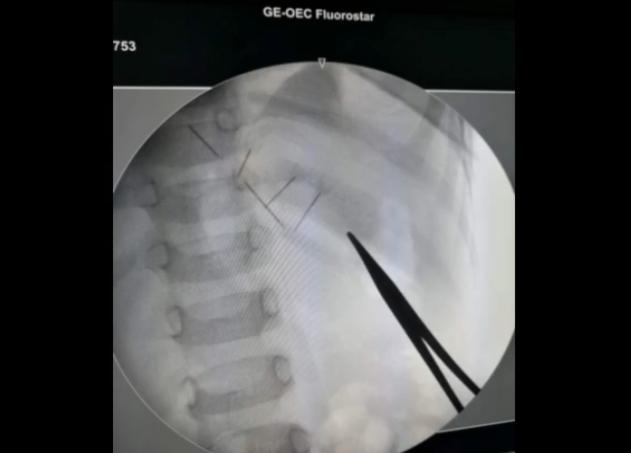

据医生介绍,根据(x光机)定位定了异物的位置,把它取出来, 取的过程中发现针已经生锈,断了几节了,这也意味着,每取一节要重新定位!所幸手术进展的非常顺利,医生从宝宝体内取出了断成了四节的缝衣针。